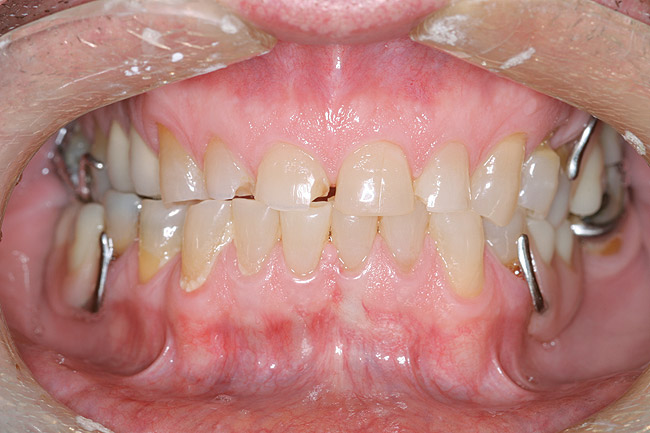

Figure 12 through Figure 14 Final restoration of the severe wear case seen in Figure 9 through Figure 11. The incisal edge position was maintained.

Figure 12

Figure 13

Figure 14

This author has found that a good starting point for the central incisor length is 10.5 mm. The “E” and rest positions are then used to determine the approximate vertical position to place the incisal edge. In many cases involving tooth wear, the patient will want longer-looking teeth. Simply adding length to the incisal to achieve 10.5 mm will often result in encroachment on the envelope of function and the neutral zone. Phonetically, the position of the incisal edge is important when considering the lower lip. The lower lip must interact with the incisal edge in a natural, effortless fashion. This is evident during the pronunciation of words beginning in the letters “V” and “F” (Figure 8). The incisal edge contact should occur in the moist or inner vermilion border of the lip and not the cutaneous or dry portion. This error can often been seen in restorations that are too long incisally.6 The patient in Figure 9 has obviously been occlusally compromised and has extreme wear. However, consider the patient’s current incisal edge location seen in the “E” position (Figure 10). The current position is very close to the ideal vertical position. If an ideal incisor length is to be achieved, the length must be captured from the apical direction. This particular case is an example of passive delayed eruption. As the teeth slowly wear, the alveolar process migrates to keep pace with the tooth loss. The cementoenamel junction, soft tissue attachments, and incisal edge position stay anatomically in place as the process migrates.11 The final restorative process for this patient included hard tissue crown lengthening to recapture added tooth length (Figure 11) and maintenance of the current incisal edge position. The proper maxillary occlusal plane, envelope of function, and anterior guidance were then restored. All of the above parameters were established in the diagnostic phase and then tested in long-term provisionals. The final restorative result can be seen in Figure 12 through Figure 14.